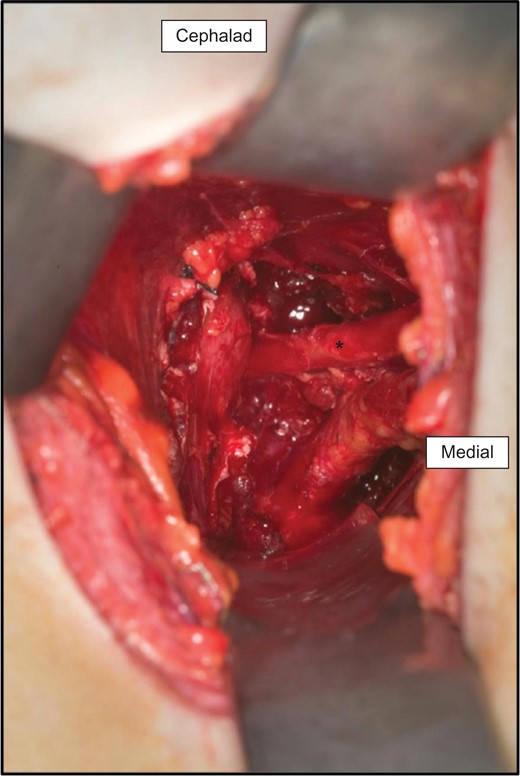

Under general anesthesia in left lateral decubitus, a transverse incision was made in the axilla with dissection carried down to the thoracic outlet. The anterior and middle scalenes were identified and resected. The large callus on the first rib was identified and located adjacent to the neurovascular bundle consistent with preoperative imaging (Fig. 2). The rib was then circumferentially isolated and resected with a rib cutter, however the posterior-most portion of the rib was inaccessible. Therefore a rongeur was used to remove remaining bone. On inspection of the specimen, a large protuberance corresponding to the callus on MR was immediately obvious (Fig. 3). The neurovascular bundle was identified and protected throughout the resection. There was obvious entrance into the chest so a chest tube was place. The patient was woken and had an intact neurological and vascular exam. Postoperative chest film showed adequate removal of the first rib.